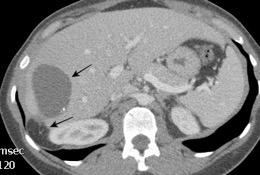

29. FALSA ELEVACIÓN DIAFRAGMÁTICA. GRASA

Ghonge NP. Hepatodiaphragmatic fat interposition' and 'increased right hemidiaphragmatic thickness': new imaging signs for early diagnosis of hepatic cirrhosis on routine CT abdomen. Abdom Radiol 2020.

Grasa simulando elevación diafragmática izquierda